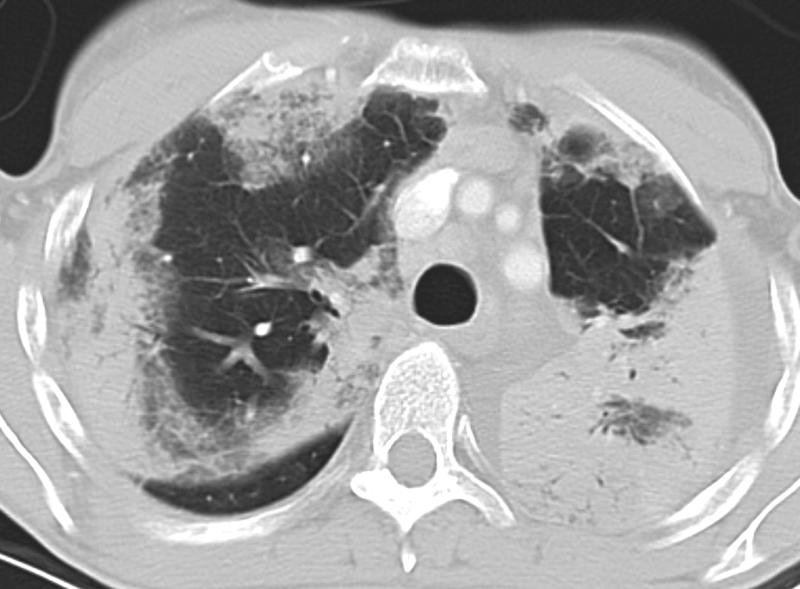

Pneumonia

Eos Pneum (AEP) CT

Date: 03/11/2006